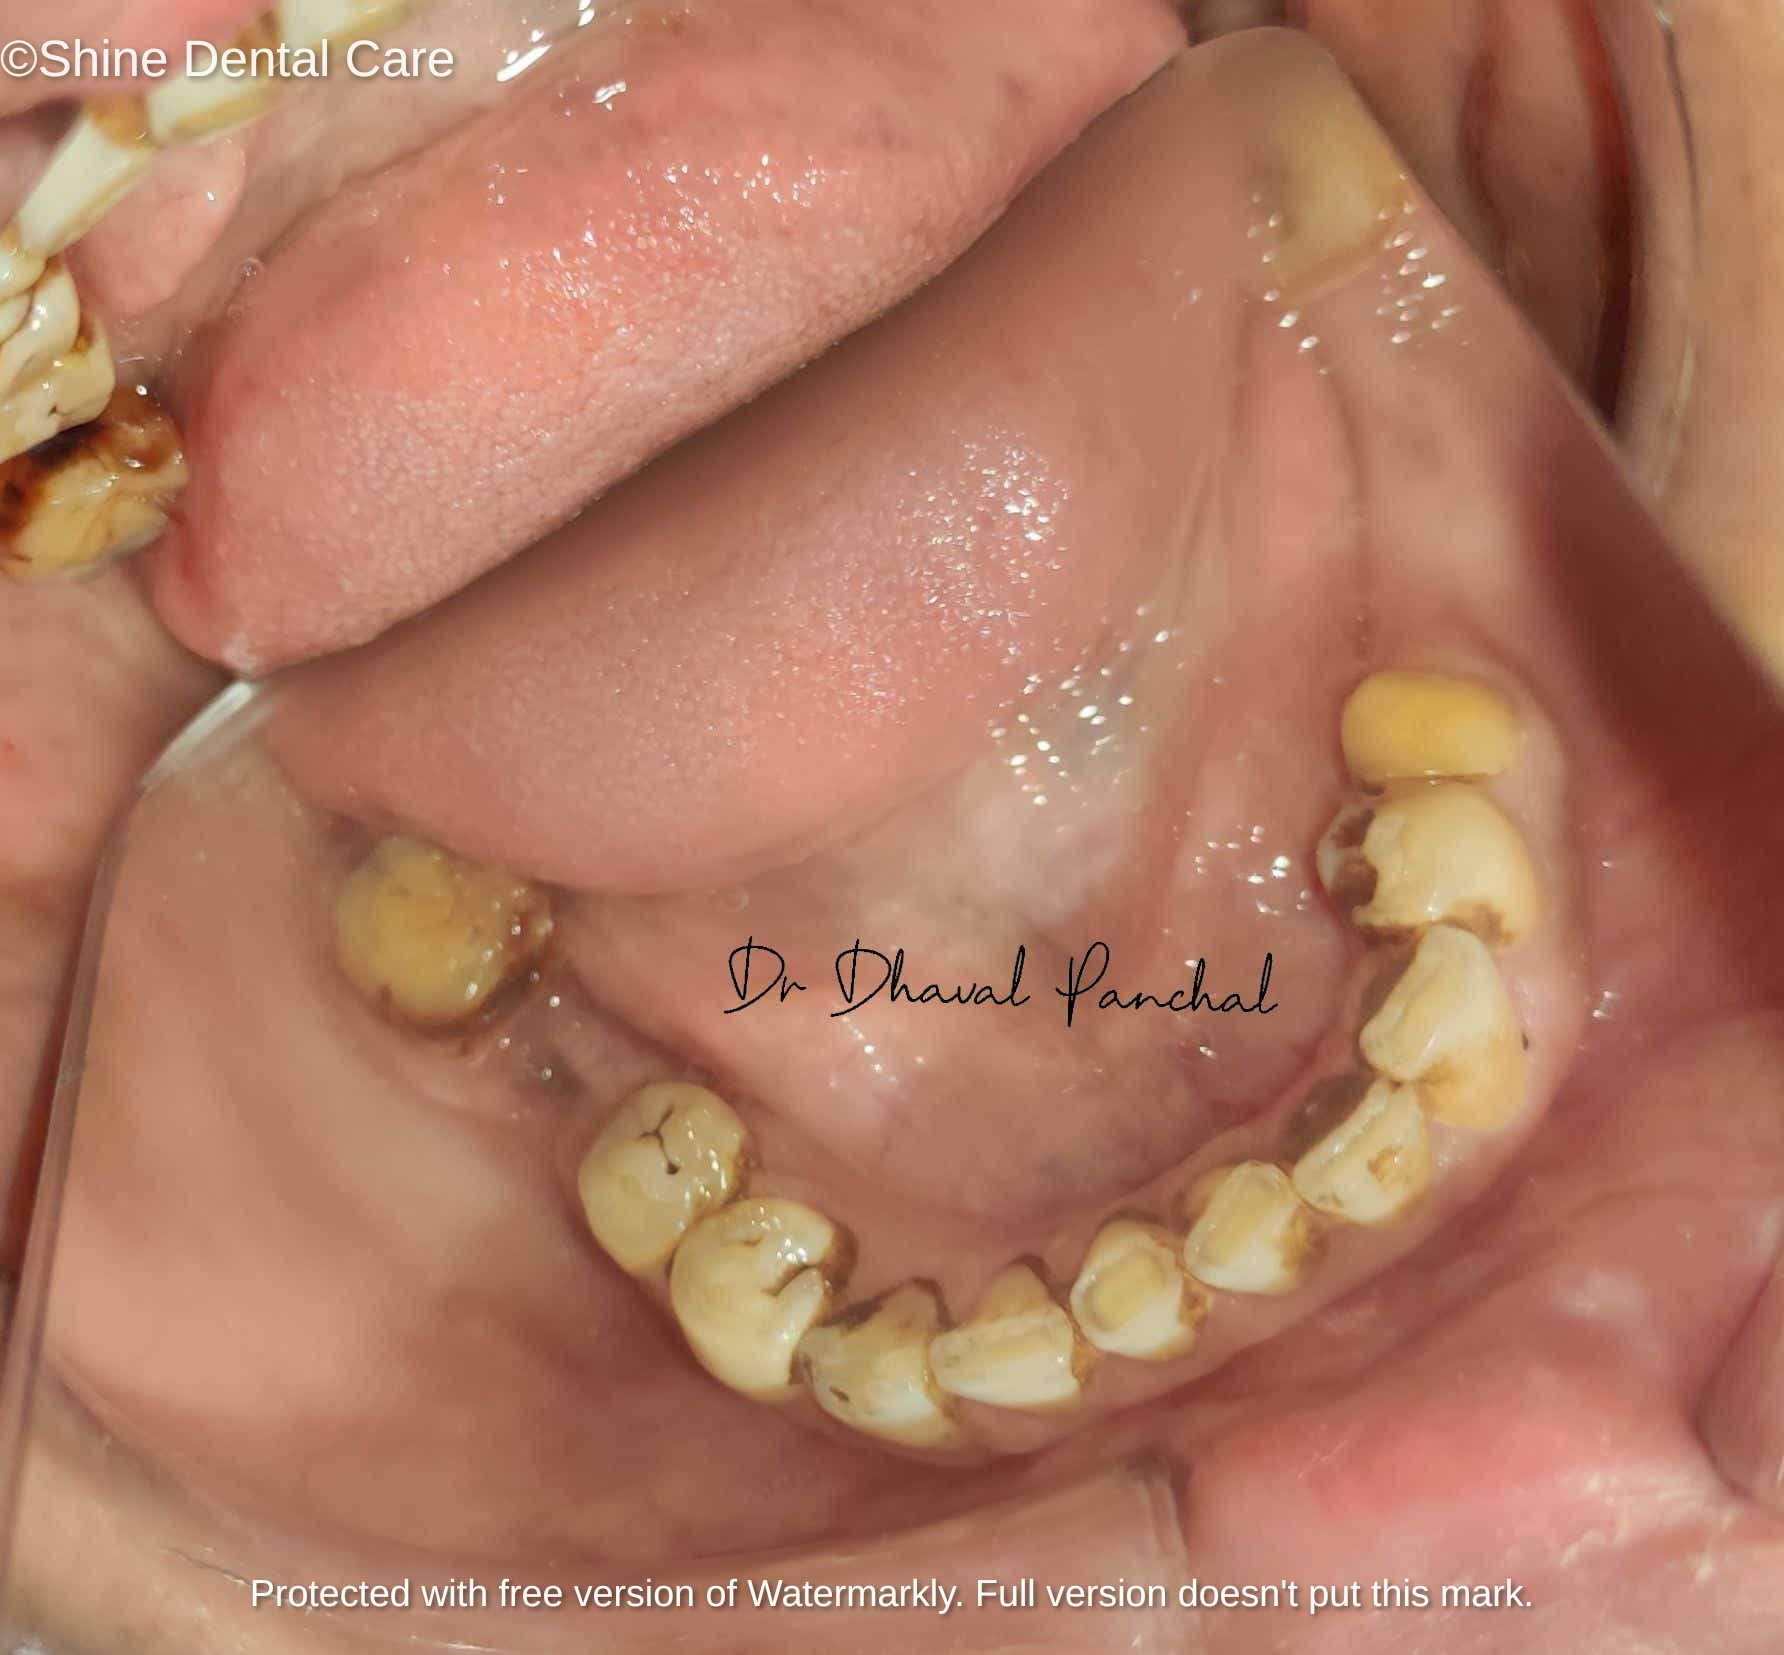

Full Mouth Rehabilitation

As the name implies, Full Mouth Rehabilitation refers to rebuilding and/or replacing all of the teeth ina patient’s mouth. Full Mouth Rehabilitations combine esthetics with the science of restorative dentistry to improve the health, function, and beauty of the mouth.

There are a number of people who have dental problems throughout their mouths that must be treated comprehensively with a vision of a final result that improves both function and esthetics. These patients may exhibit multiple missing teeth, numerous teeth with large fillings that are failing or exhibiting decay, cracked or broken teeth, or badly worn teeth due to bruxism (teeth grinding) or other habits.